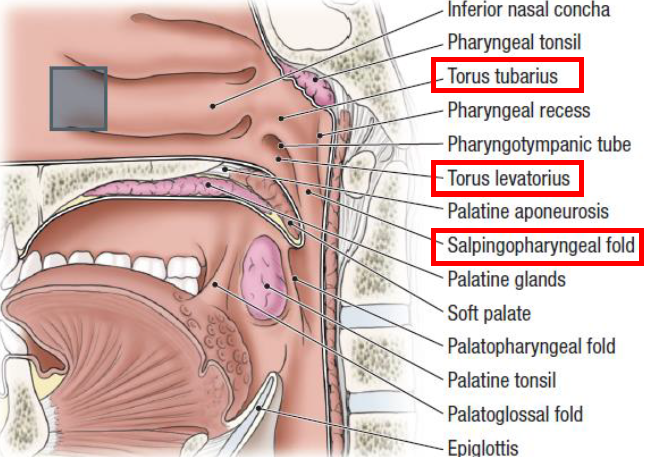

Nasopharynx

Sensor:CN V

- Opening of Pharyngotympanic tube (auditory tube, Eustachian tube)

- 前:Salpingopalatine fold

- 後:Torus tubarius Salpingopharyngeal fold

- Pharyngeal tonsil

Pharyngotympanic tube

- 通過 Temporal bone

- 後2/3是軟骨

- 通過 Temporal bone

- 後2/3是軟骨

- Levator veli palatine m.

- From Scaphoid fossa

V3支配

- Tensor veli palatini m.

- 增加軟顎強度

- 打開耳咽管

- 繞過 pterygoid process